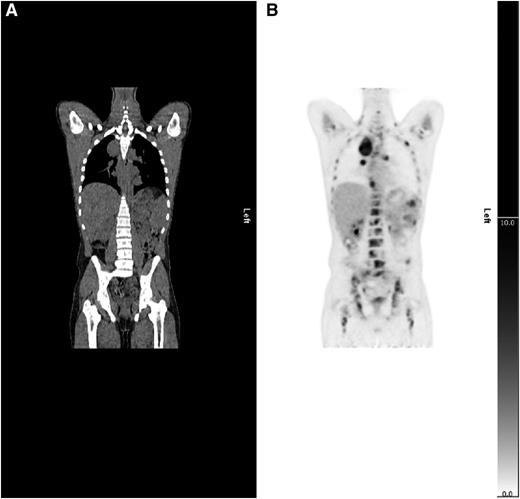

Example of upstaging by PET-CT. (A) CT and (B) PET coronal images show a case upstaged by PET-CT. Nodal and splenic involvement was reported on CT and interpreted as stage 3. The PET scan showed multifocal uptake in bone marrow upstaging to stage 4.